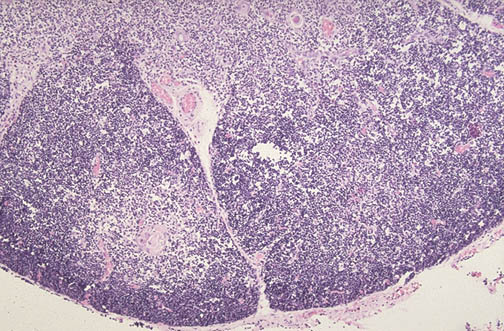

| At low power the thymus is seen to be pale because of reduced numbers of lymphocytes. The infant manifested problems with cell-mediated immunity. This is partial DiGeorge syndrome. Most cases of DiGeorge syndrome result from a deletion of chromosome 22q11.2 (the DiGeorge syndrome chromosome region, or DGCR). Manifestations of the 22q11 deletion syndrome include congenital heart disease (such as tetralogy of Fallot), palatal abnormalities such as cleft palate, facial abnormalities, and learning difficulties. Parathyroid hypoplasia (with hypocalcemia) and thymic hypoplasia (DiGeorge anomaly) are seen in some cases of 22q11 deletion. |